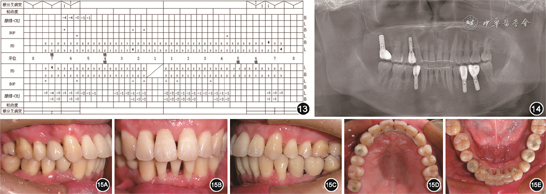

(6)牙周维护治疗:2020年5月正畸结束,上下前牙舌侧丝固定。11、21间牙槽骨垂直向高度恢复,牙龈乳头充盈良好(图12)。局部牙龈充血红肿,全口牙周维护治疗后,完成种植体上部修复,嘱患者每3~4个月牙周复查。正畸结束9个月随访复查时全口牙周状况良好,牙列整齐,种植体无松动,牙龈无红肿,咬合关系正常,患者对治疗效果满意(图13, 14, 15)。

综上,本病例在恢复牙周组织健康、重建咬合功能及改善前牙美观方面均获得良好疗效,可为重度牙周炎的多学科诊治提供临床思路。完善的牙周基础治疗、个性化的治疗方案设计及患者良好的依从性是获得理想疗效的关键。本病例随访时间较短,后续将继续随访观测其长期预后。